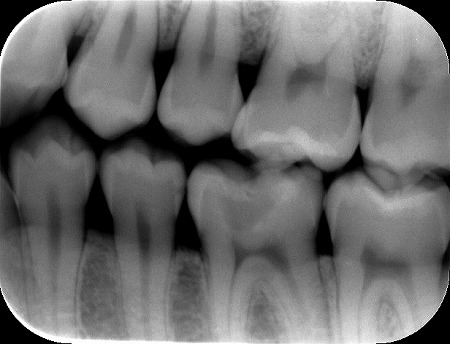

今日もそんな患者様がいらっしゃいました。下の写真です。

麻酔をして、プラスチックを外すと、前回のように虫歯が拡がってボロボロというほどではなかったのですが、歯質はかなり溶けて軟らかくなっていました。

これで痛みが有れば、神経を殺さないと痛みは取れません。前回の1月15日の方は痛みが有ったので仕方なく神経を取りました。今回は、まったく痛みは無く、検診の意味と他の歯の虫歯のレントゲンを撮った時に、たまたま見つかった虫歯でした。早期発見でしたので痛みはありませんが、悪い虫歯の所を削っていくと神経にかかりそうでした。こんな時に有効なのが3Mix法という神経を助ける治療方法があります。